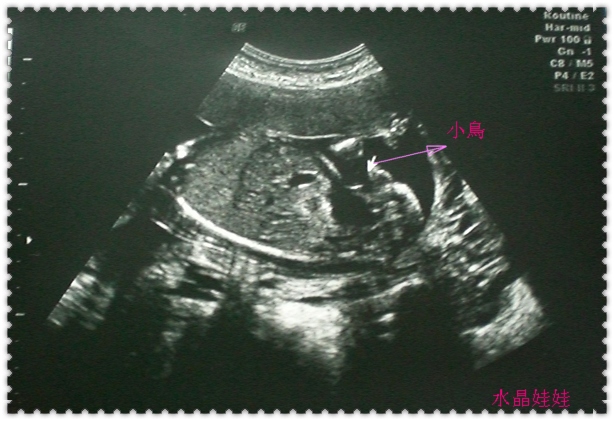

從多錢的頭圍、肚圍、四肢、耳朵、嘴唇、生殖器與蛋蛋、

到腦部、各內臟器官的狀況、血流狀況都檢查過ㄧ次。